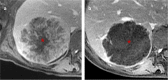

Colorectal liver metastases (CRLM) have heterogenous histopathological and immunohistochemical phenotypes, which are associated with variable responses to treatment and outcomes. However, this information is usually only available after resection, and therefore of limited value in treatment planning. Improved techniques for in vivo disease assessment, which can characterise the variable tumour biology, would support further personalization of management strategies. Advanced imaging of CRLM including multiparametric MRI and functional imaging techniques have the potential to provide clinically-actionable phenotypic characterisation. This includes assessment of the tumour-liver interface, internal tumour components and treatment response. Advanced analysis techniques, including radiomics and machine learning now have a growing role in assessment of imaging, providing high-dimensional imaging feature extraction which can be linked to clinical relevant tumour phenotypes, such as a the Consensus Molecular Subtypes (CMS). In this review, we outline how imaging techniques could reproducibly characterize the histopathological features of CRLM, with several matched imaging and histology examples to illustrate these features, and discuss the oncological relevance of these features. Finally, we discuss the future challenges and opportunities of CRLM imaging, with a focus on the potential value of advanced analytics including radiomics and artificial intelligence, to help inform future research in this rapidly moving field.